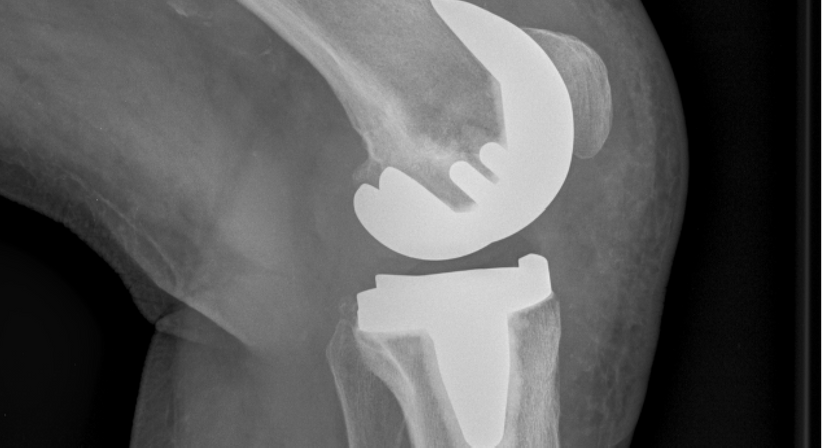

Totalendoprothese (Knie-TEP)

Eine Totalendoprothese des Knies, auch als Knie-TEP abgekürzt, ist ein chirurgischer Eingriff, bei dem das gesamte Kniegelenk durch eine künstliche Prothese ersetzt wird. Die Prothese besteht aus Metall und Kunststoff und ahmt die natürliche Struktur und Funktion des Kniegelenks nach.